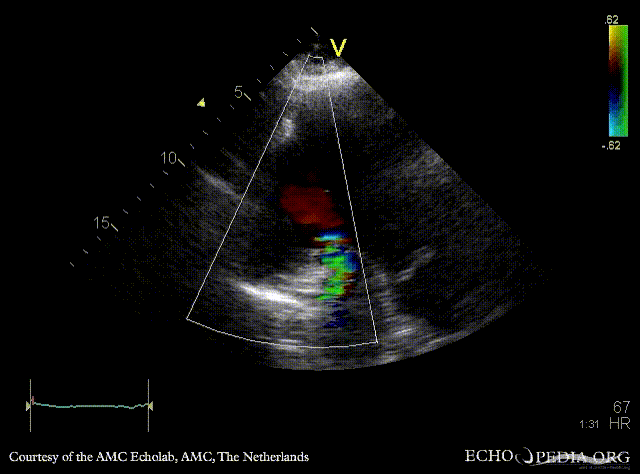

A3CH: large pseudoaneurysm of posterior wall, spontaneous echocontrast A3CH: Color Doppler, severe mitral regurgitation